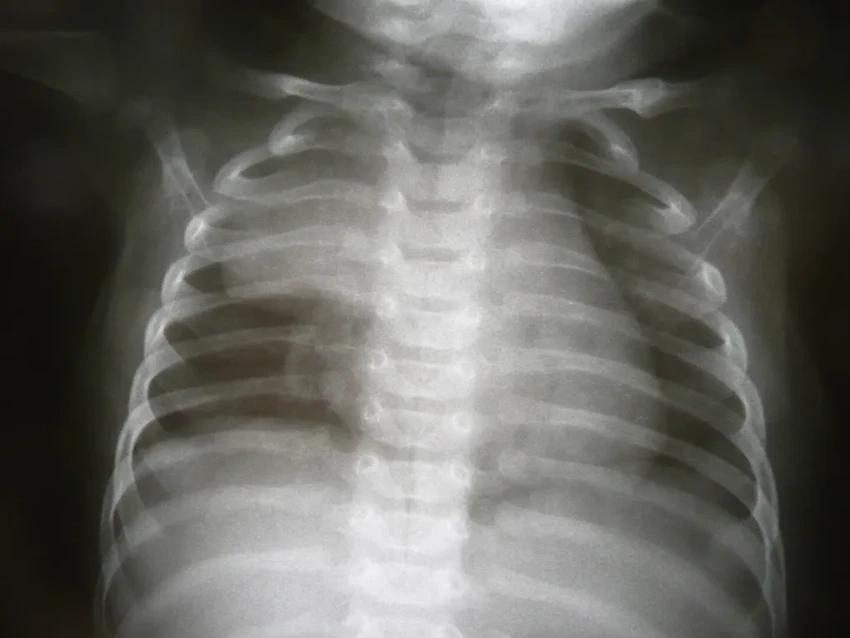

Всем известно, что в детстве тимус — настоящая «школа» для иммунитета. Именно здесь созревают Т-лимфоциты — те самые клетки-защитники, которые борются с инфекциями и болезнями. Если железу удалить в молодом возрасте, количество и разнообразие этих клеток остаётся сниженным на всю жизнь.

- Дети без тимуса даже хуже реагируют на прививки — их иммунная система просто не может правильно «запомнить» врага. Считалось, что к половозрелому возрасту железа «выполняет свою миссию», сморщивается и становится почти бесполезной. Её даже начали иногда удалять «заодно» во время операций на сердце — она ведь мешает хирургу, верно? Но так ли это на самом деле?